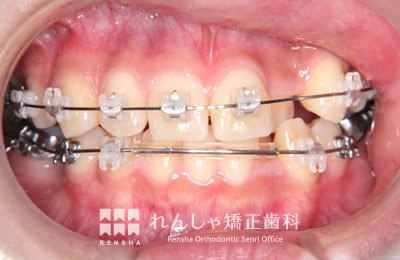

中高生

永久歯列はほぼ完成してしますが、歯列を側方だけでなく後方へも拡大し、埋まっていた右上奥歯を引っ張り出しています。

| 主訴 | 埋まったままでてこない歯がある |

|---|---|

| 診断名 | Angle Class II 小臼歯の埋伏と叢生を伴う上顎前突 |

| 初診時年齢 | 13歳5か月 |

| 装置名 | マルチブラケット装置 |

| 抜歯非抜歯 | 非抜歯 |

| 治療期間 | 2年3か月 |

| 費用の目安 | 約82万円+消費税(検査料金、都度の処置費用等も合わせた総額) |

| リスク副作用 | 歯の移動に伴う軽微な歯根吸収、歯槽骨吸収、歯肉退縮(本症例では軽度の歯根吸収を認めた)、矯正器具装着中のカリエスリスク増大(本症例ではカリエス発生無し) |